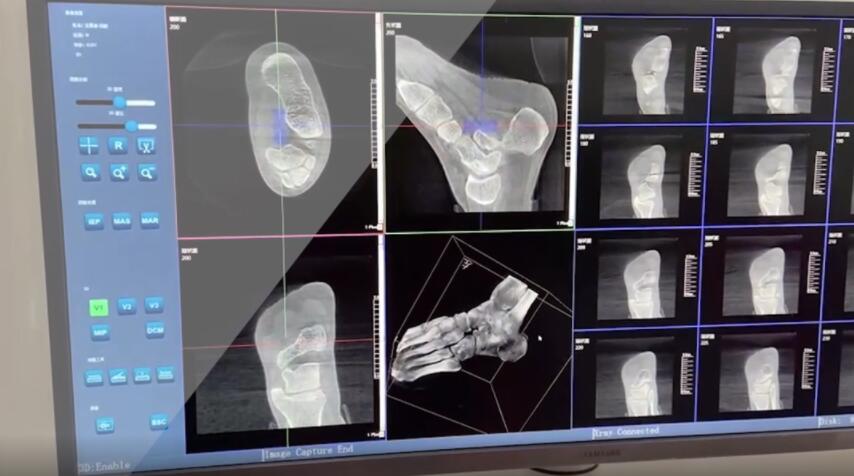

踝關節是人體中負重較大的關節,也是活動度較大的地方,所以對于足踝部位的關節內骨折,我們更需要做到“解剖復位”。對于這種關節內的骨折,尤其是踝關節內部的骨折,不僅需要進行X影像平片正側位的拍攝,由于在二維影像上無法判斷關節面的受損情況,往往還需要進行三維影像的檢查。

在術前,我們需要做三維掃描的CT檢查,我們必須要有CT的片子,還要有三維的重建。

在術中,我們怎么去判斷關節面平不平整呢?常規的正側位影像是不能判斷的。有些醫生為了準確的判斷,可能會選擇做開放性的手術,把關節暴露出來,在眼睛的直視下判斷關節面平不平整。但是關節全部打開,無疑增加了病人的創傷,而且增加了患者的恢復時間。所以如果在術中我們有三維影像的支持,對醫生做手術而言就會事半功倍,而且能夠大大的增加手術準確度,增加患者術后的預后。所以在術中有三維影像的支持是非常必要的!

三維影像 看透關節內骨折的“眼睛”